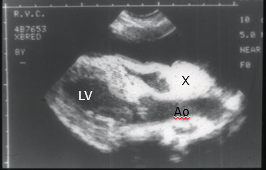

What is this view showing?

View you would get through lateral

Can get at most of pericardium and at a patent ductus arteriosus

Can also see the phrenic nerve running